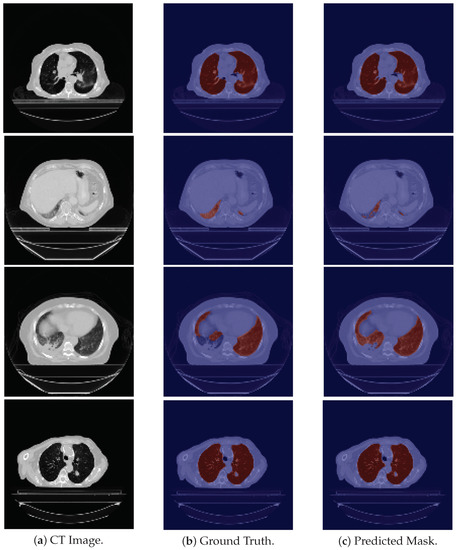

With respect to the 24-LCTSC dataset, the model is generally able to correctly segment the pulmonary images (see the first row in Figure 2), but fails to identify their initial slices, which correspond to the base of the lung, leading to a decrease in the DSC (see the second row in Figure 2). Furthermore, for one of the patients, the masks produced by the model seem to be more accurate than the ground truth images, as the latter excludes part of the lung parenchyma. An example is shown in the third row in Figure 2. Therefore, even though this contributes to a lower DSC due to the discrepancy between them, the predicted mask is more precise. On the other hand, there are cases in which nodules are not included in the ground truth, and there are elements that the model does not include as well, giving rise to a higher DSC, although incorrectly classified. An example is depicted in Figure 2, fourth row.

Figure 2. Examples of LCTSC images, the ground truth and the predicted mask. From top to bottom the examples are, respectively: good segmentation example; an example in which the model fails to segment the base of the lung; an example of a ground truth image that excludes part of the parenchyma of the lung; an example that excludes a nodule in its ground truth, and which is also misclassified by the model.